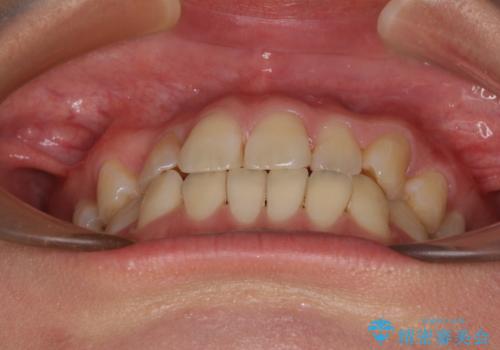

上下前歯のデコボコを気にして来院された患者様です。

ワイヤー矯正でもマウスピース矯正でも可能でしたが、短期間で、自身の手を煩わせることなく治療を行いたいとのことで、ワイヤー装置にて矯正治療を行うこととしました。

舌の突出癖により、治療過程でスペースが多くできましたが、舌のトレーニングを頑張っていただき、1年強で終えることができました。